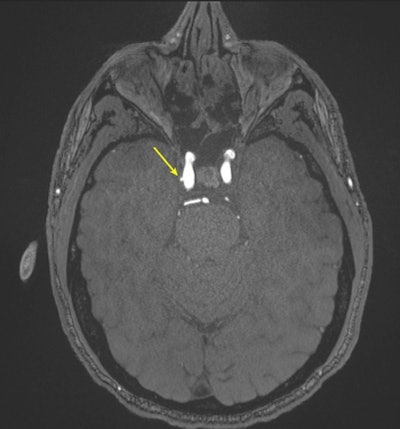

Representative axial time-of-flight MR angiography image in a 39-year-old male participant shows a laterally projecting intracranial aneurysm (arrow) originating from the right cavernous segment of the internal carotid artery.Representative axial time-of-flight MR angiography image in a 39-year-old male participant shows a laterally projecting intracranial aneurysm (arrow) originating from the right cavernous segment of the internal

carotid artery.